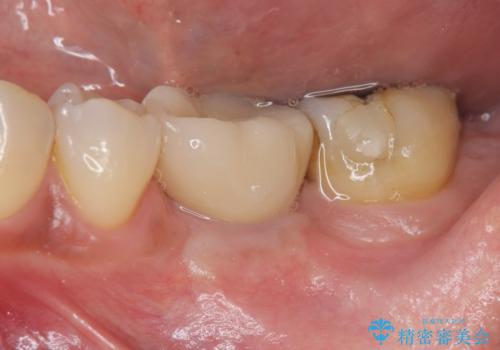

[ 歯槽堤保存術 ] [ 奥歯の破折 ] ソケットプリザベーションを併用したインプラント治療